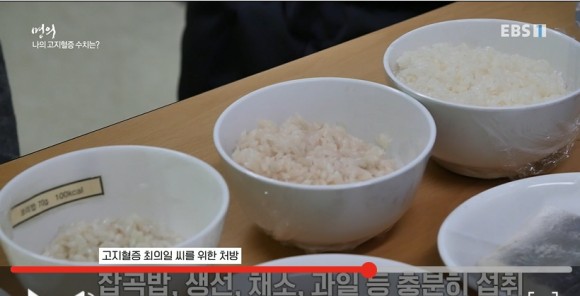

무조건 약을 먹는 것보다 2주간 생활습관 개선을 먼저 시도하고 콜레스테롤 수치 변화를 관찰합니다. 잡곡밥, 생선, 채소, 과일 등을 충분히 섭취하고 육류, 기름진 음식, 버터 제한합니다. 하루 세 번 식사, 인스턴트 안 먹기, 식후 운동(301시간 걷기, 근력운동) 등.

고지혈증 환자의 식단

고지혈증 환자는 무조건 포화지방을 줄여야 합니다. 포화지방이란 상온에 두었을 때 딱딱해지는 지방으로 육류의 지방, 버터, 치즈, 라면 등에 많습니다.컵라면 포화지방 6.4g, 햄버거 포화지방 6.1g, 포화지방 1일 권장량은 15g인데 성인 1일 섭취량은 59.3g이나 됩니다.Q. 포화지방 섭취를 어떻게 줄일까?과도한 탄수화물, 설탕, 밀가루 등을 불포화 지방산 섭취로 바꾸는 것입니다. 들기름, 견과류, 생선 등 즉 우리가 먹는 음식에서 10%만 불포화지방으로 바꿔도 되는 콜레스테롤인 HDL은 10% 상승, 중성지방과 LDL은 20% 이상 낮아지는 효과가 있습니다.

먹는 양을 줄이기보다는 지금까지 먹던 음식을 단백질이나 무기질 중심으로 바꾸는 겁니다.Q. 고지혈증약의 부작용은 괜찮습니까?고지혈증약은 스타틴이라는 약으로 국내 100만명의 환자가 복용 중인 안전한 약이지만 부작용도 있습니다.